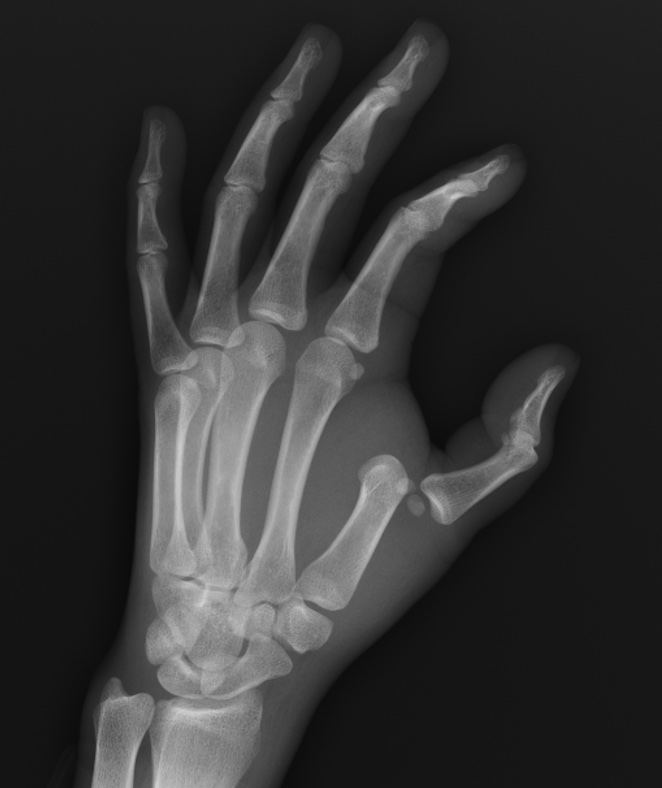

A healthy 22 yo female presents to the ED with left thumb pain. She was jogging and tripped and used her left hand to break her fall. An x-ray is shown. What's the diagnosis? Scroll down for answer.

Answer: Dislocation of the first metacarpophalangeal joint

- Occurs with hyperextension injuries, most dislocations occur dorsally

- Most commonly involves the index finger

- Simple dislocation

- More apparent clinical appearance - the MCP joint is in 60-90 degrees of hyperextension

- Complex dislocation

- More subtle appearance - the phalanx is almost parallel to the metacarpal

- Almost impossible to reduce

- Reduction technique: further hyperextension with pressure at the base of the phalanx

- After successful reduction immobilize with MCP flexed at 60 degrees

- Higher incidence of irreducible dislocations (compared to PIP or DIP joint dislocations)

- consult hand surgery if unable to reduce